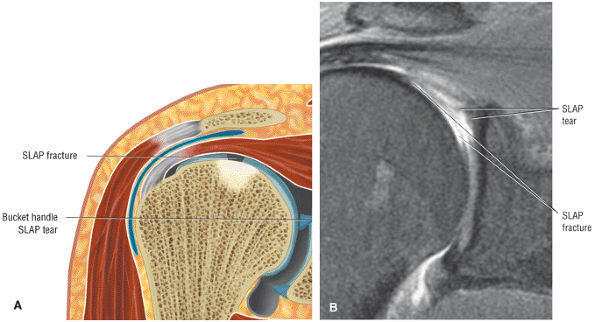

The SLAC lesion is combined with the anterior component of a SLAP 2 tear.

-

The SLAC lesion is a type of instability and not an impingement lesion.

![]() |